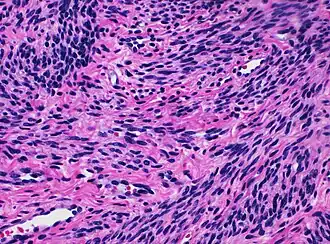

![]() Histology of myometrium | |

The myometrium is the middle layer of the uterine wall, consisting mainly of uterine smooth muscle cells (also called uterine myocytes[1]) but also of supporting stromal and vascular tissue.[2] Its main function is to induce uterine contractions.